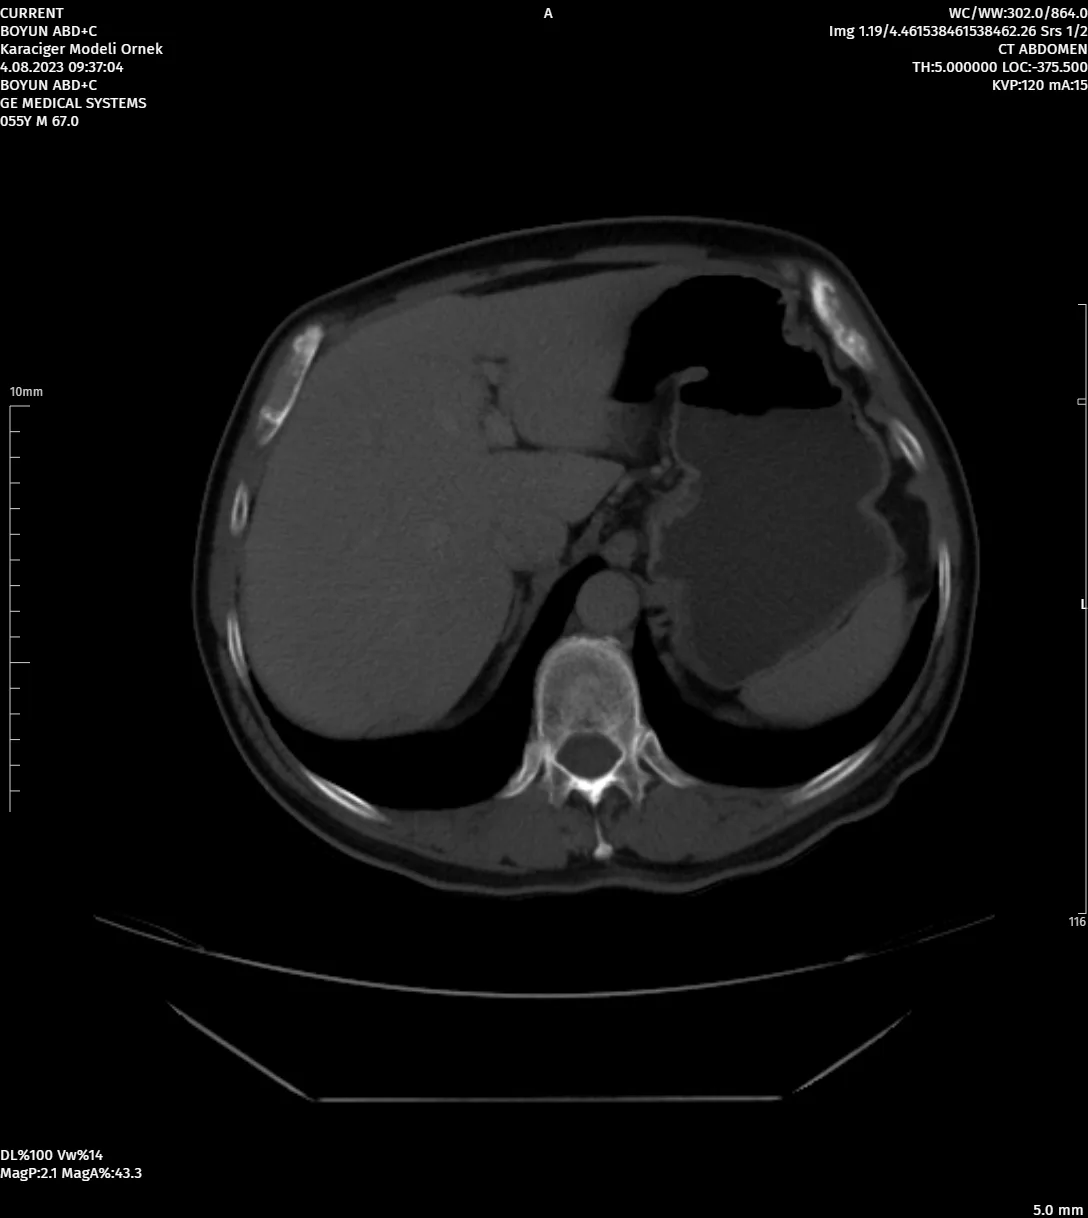

DevamıGelişmiş Görüntü İşleme Araçları

Farklı Segmentasyonlar ile Çalışabilen Görüntü İşleme Araçları